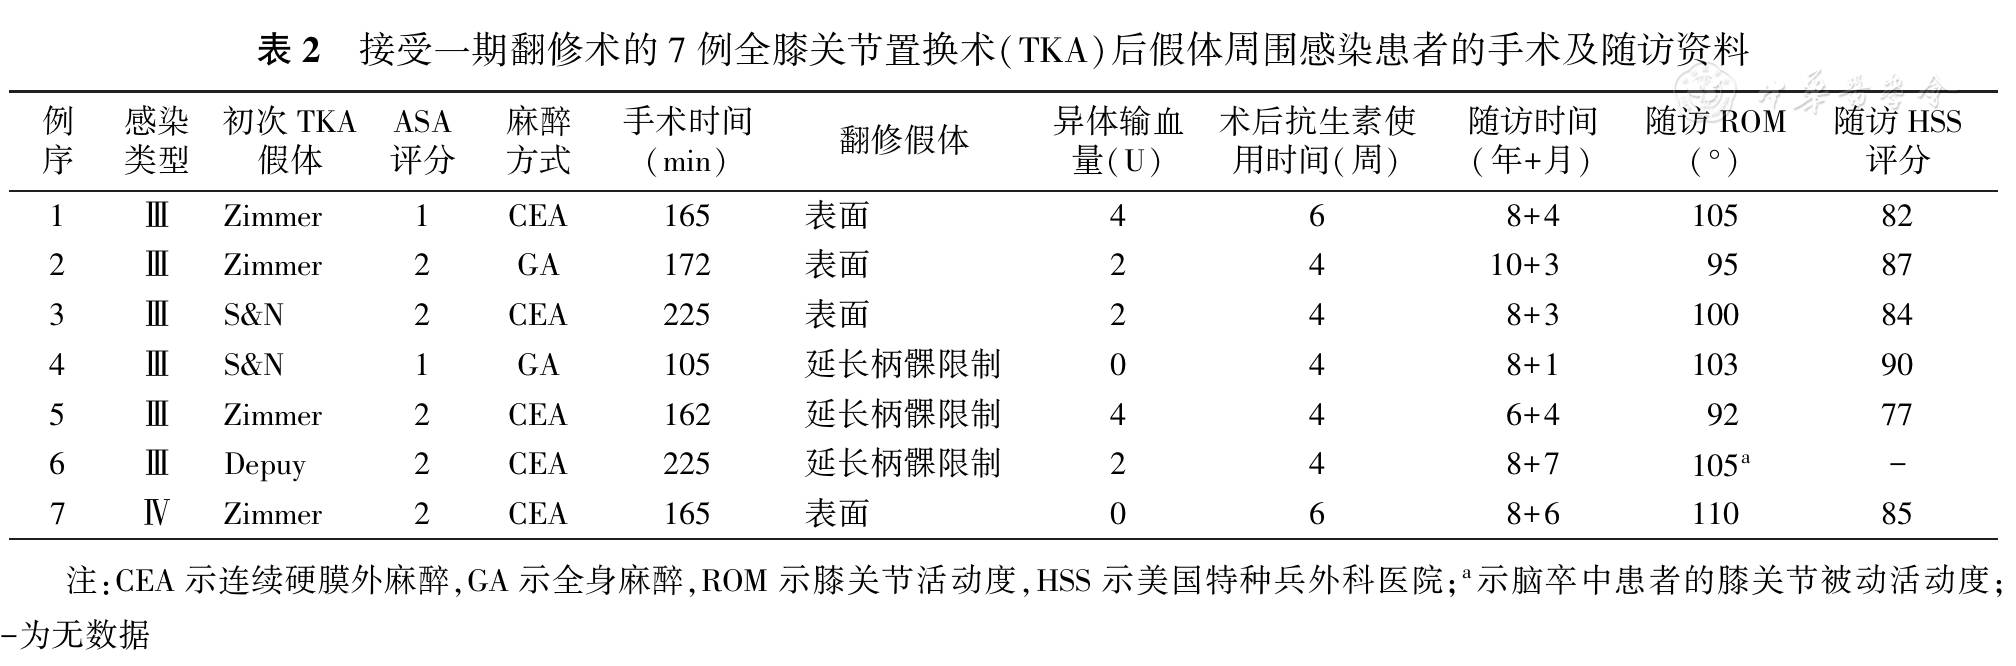

一期翻修术治疗全膝关节置换术后假体周围感染的中长期随访结果

一期翻修术治疗全膝关节置换术后假体周围感染的中长期随访结果